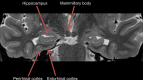

Neurodegenerative diseases are a devastating group of disorders that can be difficult to accurately diagnose. Although these disorders are difficult to manage owing to relatively limited treatment options, an early and correct diagnosis can help with managing symptoms and coping with the later stages of these disease processes. Both anatomic structural imaging and physiologic molecular imaging have evolved to a state in which these neurodegenerative processes can be identified relatively early with high accuracy. To determine the underlying disease, the radiologist should understand the different distributions and pathophysiologic processes involved. High-spatial-resolution MRI allows detection of subtle morphologic changes, as well as potential complications and alternate diagnoses, while molecular imaging allows visualization of altered function or abnormal increased or decreased concentration of disease-specific markers. These methodologies are complementary. Appropriate workup and interpretation of diagnostic studies require an integrated, multimodality, multidisciplinary approach. This article reviews the protocols and findings at MRI and nuclear medicine imaging, including with the use of flurodeoxyglucose, amyloid tracers, and dopaminergic transporter imaging (ioflupane). The pathophysiology of some of the major neurodegenerative processes and their clinical presentations are also reviewed; this information is critical to understand how these imaging modalities work, and it aids in the integration of clinical data to help synthesize a final diagnosis. Radiologists and nuclear medicine physicians aiming to include the evaluation of neurodegenerative diseases in their practice should be aware of and familiar with the multiple imaging modalities available and how using these modalities is essential in the multidisciplinary management of patients with neurodegenerative diseases.©RSNA, 2020.